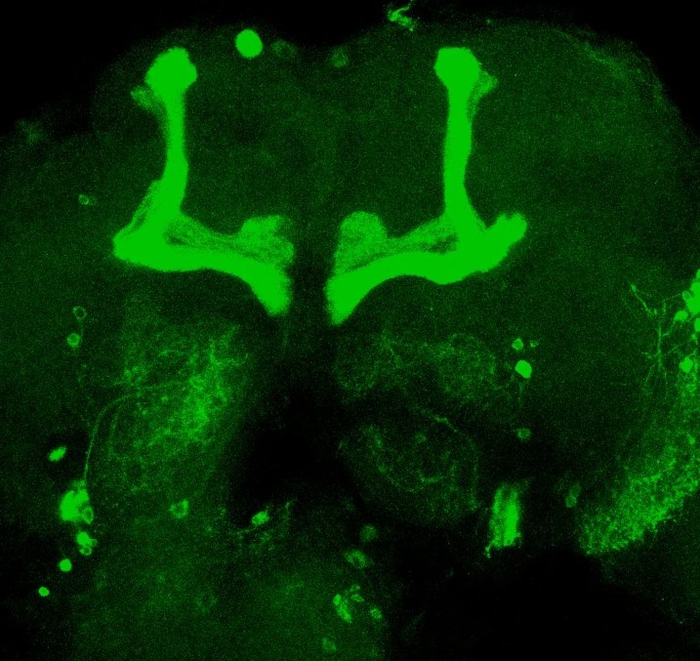

Using infrared sensors that detect the movements of flies contained in tubes, scientists can easily analyze their sleep-wake cycles. Over a 24-hour period, flies sleep for about 10 hours at night, then are active all day, except for a nap of about 4 to 5 hours. The biologists were interested in flies that have a deregulated sleep-wake cycle and whose particular area of the brain, called ‘mushroom bodies’ because of its characteristic shape, is damaged. They analyzed the expression of genes in this area of the brain of healthy Drosophila. “We identified a gene, Nf1 , whose expression fluctuates according to the sleep-wake phases of the fly: its expression increases when the flies are awake, while it decreases during their sleep”, explains Blanca Lago Solis, researcher in the Department of Genetics and Evolution. To confirm the link between this gene and the circadian rhythm, the biologists observed flies that weakly express this gene, regardless of the time of day. “These flies are totally dysregulated and have much more sleep phases”, Blanca lago Solis reports.